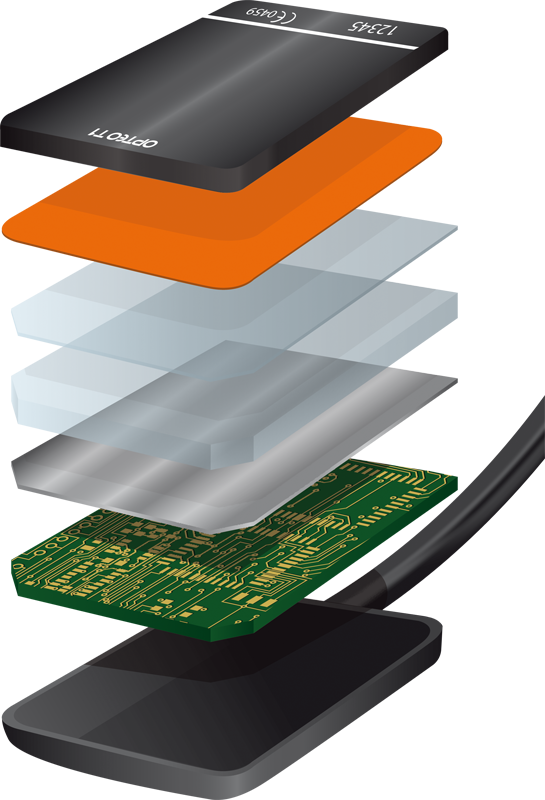

سنسور ديجيتال راديوگرافي دندان مدل Opteo T1

سنسور پنج لایه و 14 بیتی با قدرت تفکیک بیش از 16000 رنگ در حد فاصل سیاه و سفید

Full HD sensor - CMOS sensor 26.3 lp/mm

Grey levels: 14 bits - 16384 grey levels

600mm² Sensitive surface Direct USB - without box